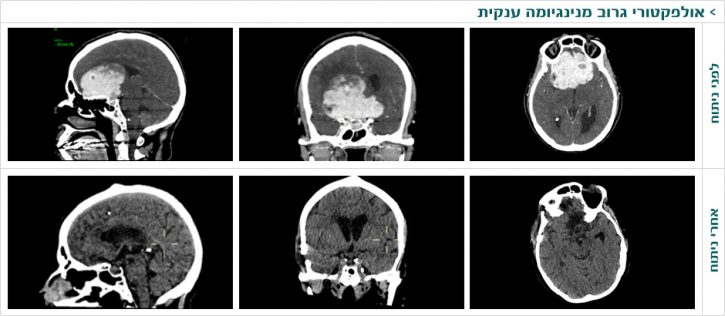

מניתוחיו של דר' עטיה: